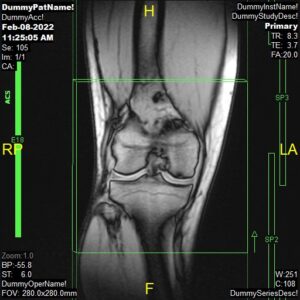

T1 Flair/Tirm Coronal, PD Coronal and PD FatSat Coronal

Parameters

Sample Image